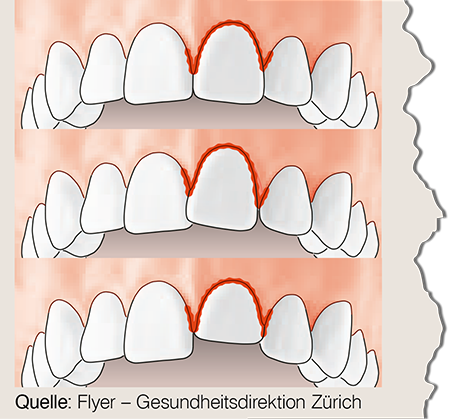

Zahn ist gelockert

Zahn ist verschoben

Zahn ist hineingeschlagen

Belassen Sie den Zahn in Position und suchen Sie umgehend Ihren Zahnarzt auf.

Behandlung ist dringend. Der Zahn muss eventuell an seinem Platz mit einer Schiene fixiert werden (innert Stunden!).

Zahn ist abgebrochen

Versuchen Sie das abgebrochene Stück zu finden!

Wenn die Möglichkeit gegeben ist, probiert der Zahnarzt dieses wieder anzukleben.

Je mehr abgebrochen, desto dringender ist die Behandlung (innert Stunden!).